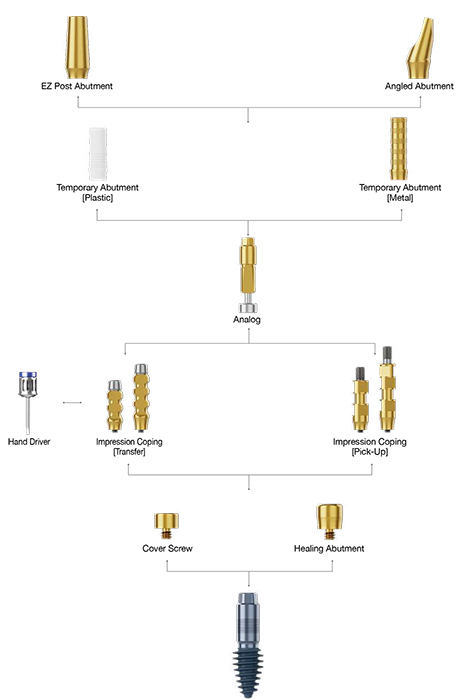

Scaling, Deep Scaling, Curettage, Implant Surgery, Implant recovery(2nd OP), Implant Hygien Care, Peri-Implantitis

- Effective cleaning of contaminated implant surfaces

- No damage to the implant surface

- Promotes osseointegration and bone regeneration